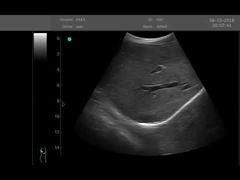

Calidad Escáner de ultrasonido portátil, analizador del ultrasonido del PDA Fabricante de China

Ultrasound scanner